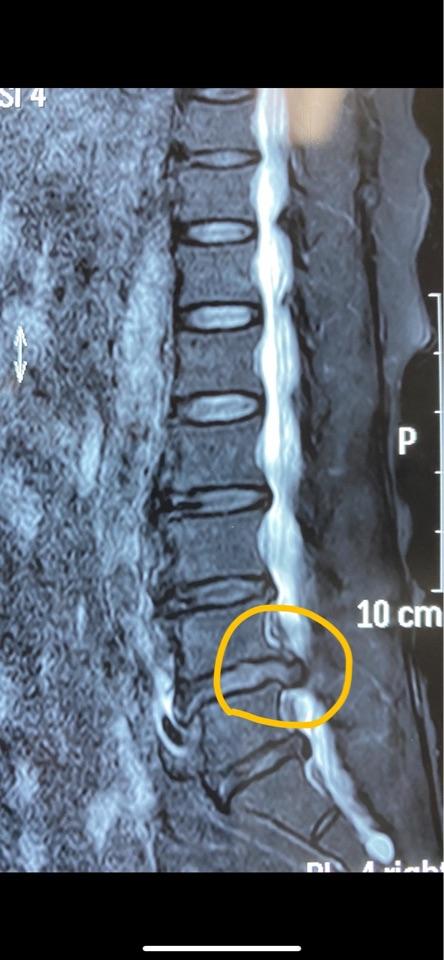

腰椎磁共振检查显示:腰4-5椎间盘突出严重,硬膜囊及神经根受压严重

磁共振轴位片发现的腰5右侧神经根上的囊肿